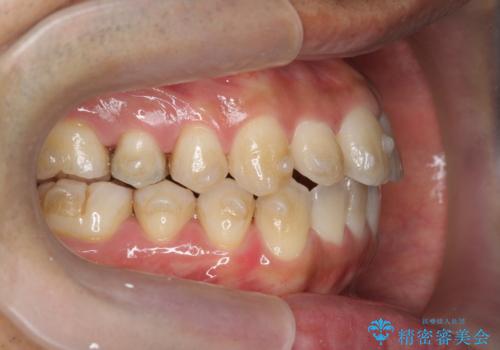

- 前歯のガタつきをきれいにしたい、と矯正治療を希望され来院されました。

マウスピース矯正インビザラインを用いてガタつきをきれいに並べていきます。

外側に傾斜していた前歯の角度も良くなり、「前歯の見た目が良くなった。」、と喜んでいただくことができました。